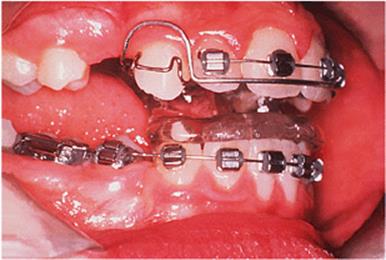

Fig. 18.2. (a)–(c) Class II division 1 malocclusion with lower arch crowding; (d) a combination of removable and fixed appliances to align the arches prior to fitting the functional appliance; (e) activator appliance modified to fit over the fixed appliance; (f) the occlusion at the end of treatment.

image(a)

image(b)

image(c)

image(d)

image(e)

image(f)

Where the premolars erupt before the pubertal growth spurt takes place, the sequence of treatment can be reversed. The crowding is relieved by extracting premolar teeth, and then the arches are aligned using fixed or removable appliances, or a combination of the two, but making no attempt to correct the incisor or molar relationships (Fig. 18.2). The functional appliance is fitted when the arches have been aligned, and some designs can be made to fit over a fixed appliance. It should be worn until the growth spurt is complete, and can serve as a retainer after the brackets have been removed.